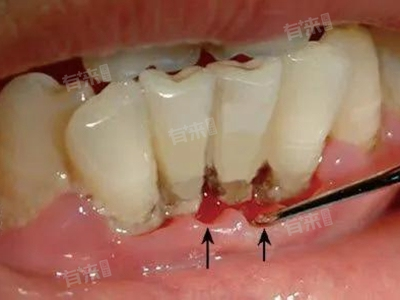

4、牙周炎:牙菌斑、牙结石等长期堆积在牙齿表面和牙周组织,引发牙周支持组织的慢性炎症。随着病情进展,牙龈退缩,牙槽骨吸收,牙根逐渐暴露,牙齿的支持组织减少,导致牙齿敏感,出现下门牙酸痛,同时患者还可能伴有牙龈出血、牙齿松动等症状。